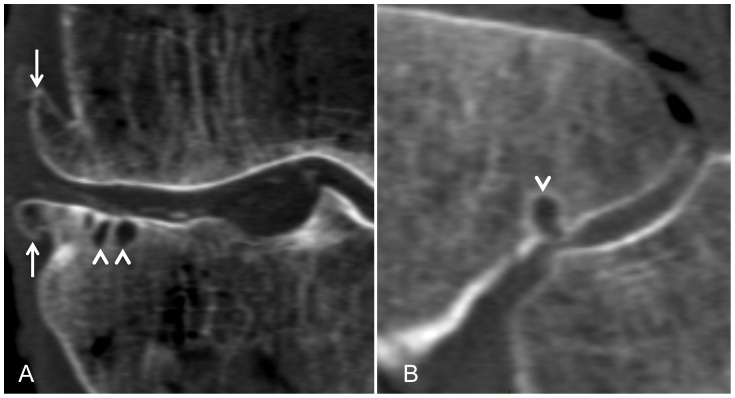

Figure 4. Computed tomographic scans of the same knee showing osteoarthritis in the medial femoro-tibial compartment on a coronal reformation (A) and in the proximal tibio-fibular joint on a sagittal reformation (B).

Osteoarthritic changes are consistent with multiple osteophytes (white arrows) and subchondral cysts (arrow heads). Articular calcifications are visible in the femoro-tibial compartment.